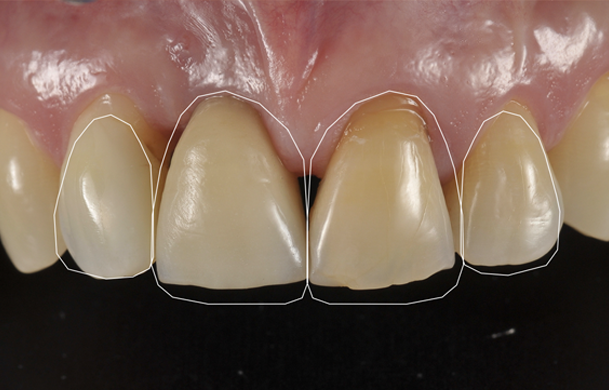

Forma, colore, proporzioni e simmetrie vengono analizzate con attenzione per armonizzare il sorriso con il volto. Ogni intervento estetico nasce da una progettazione digitale e da una sensibilità clinica orientata all’equilibrio tra bellezza e naturalezza.

Riabilitazione Estetica

Armonia tra forma, colore e proporzioni per un sorriso naturale e in equilibrio con il volto.

Faccette dentali

Soluzioni estetiche in ceramica sottile per correggere forma, colore e proporzioni del sorriso.